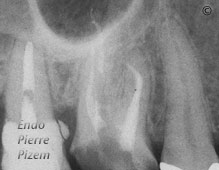

MB1 and MB2 with severe curves first right maxillary molar

You are here: Home / Curved canals / MB1 and MB2 with severe curves first right maxillary molar